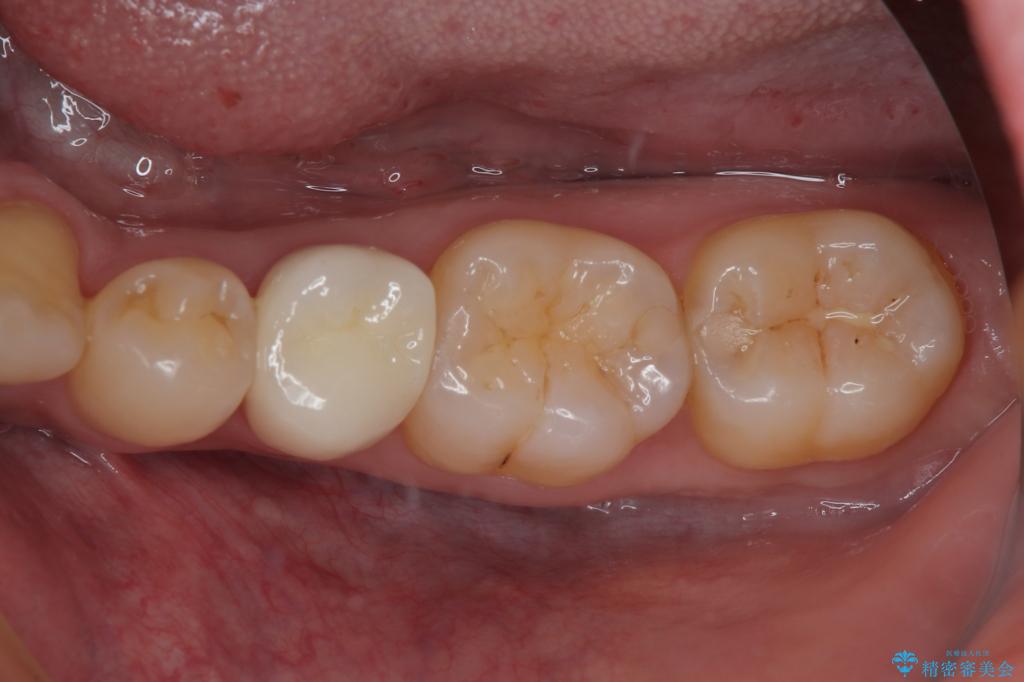

フロスがちぎれることもなくなり、被せものが入っていることを忘れていたと大変喜んでいただきました。適合の良い被せものは二次的な虫歯の再発リスクを低減してくれます。

今後の予定は患者様のタイミングで歯茎から少し見えている親知らず抜歯を行っていく予定です。